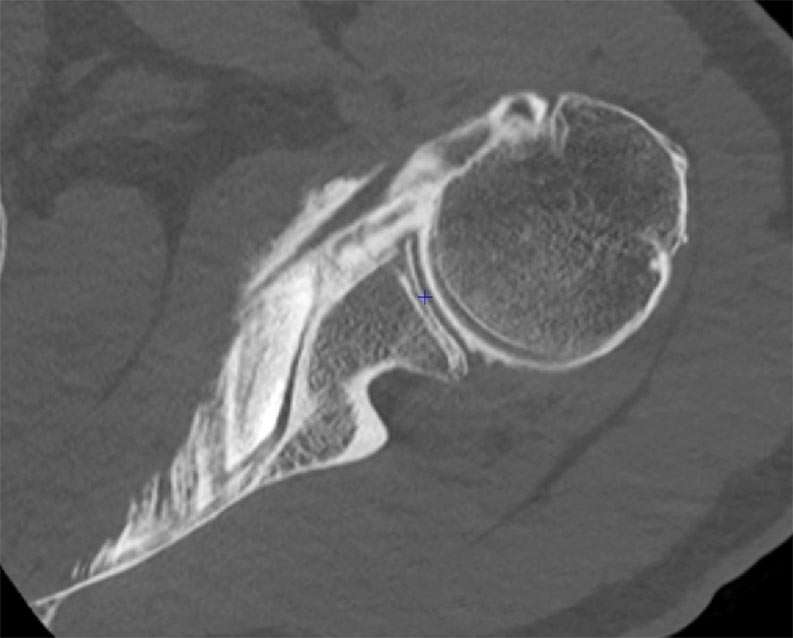

SHOULDER CASE SUMMARY:

Shoulder Left

Patient 55 y/o, Male, left-handed

History Shoulder pain for 3 years